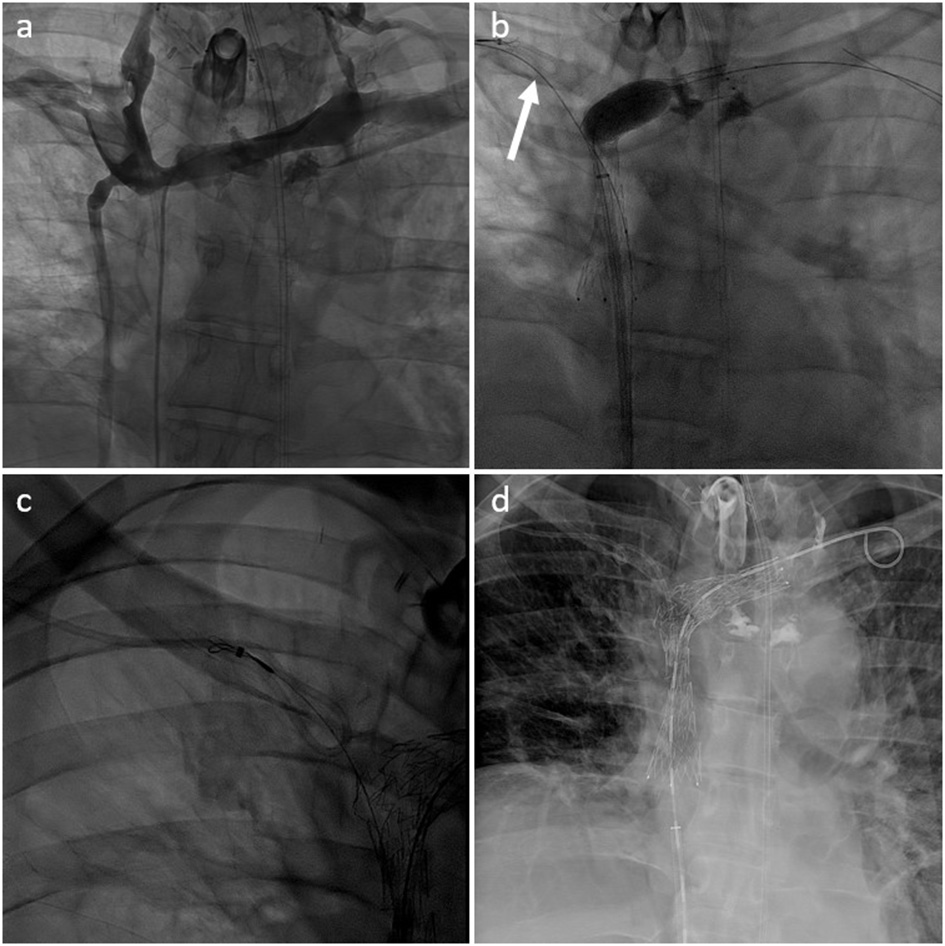

Figure 4

(a) Type IV SVCO with occlusion of the superior vena cava associated with stenosis of both innominate veins (type IV) in a patient with a left dominant jugular axis and a short implanted central venous catheter. (b) Central venous catheter was withdrawn from the superior vena cava with a snare inserted through the right arm (arrow). Recanalization and angioplasty of the superior vena cava and left innominated was performed with implantation of two overlapping stents. (c) Tip of the venous catheter was snared from the femoral venous access through the mesh of the SVC stent to allow repositioning. (d) Final result with the tip of the central venous catheter ending inside the SVC stent lumen.